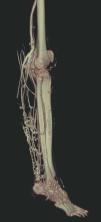

Hoy en día la utilización de los nuevos equipos TC multicorona y RM permiten la adquisición de imágenes con gran rapidez, pudiendo realizar reconstrucciones multiplanares de gran calidad, así como estudios angiográficos no invasivos13,23. Recientemente hemos estudiado 16 pacientes con síndrome de Klippel-Trenaunay mediante una venografía tomografía computarizada multicorte (TCM) o una venografía resonancia magnética tridimensional (RM-3D), utilizando imágenes axiales convencionales, reconstrucciones multiplanares (RMP), proyecciones de máxima intensidad (PMI) e imágenes tridimensionales (figs. 1-3). Las imágenes axiales convencionales fueron de utilidad para evaluar el tejido blando y el hueso y permitieron localizar el sistema venoso profundo y los vasos anómalos superficiales, determinando su relación con estructuras adyacentes. Las imágenes axiales, RMP y PMI fueron empleadas para trazar el origen, trayecto y extensión de las malformaciones venosas. Las imágenes de la superficie cutánea permitieron evaluar la localización y la extensión de la mancha en vino de Oporto y demostrar la hipertrofia de la extremidad. Las reconstrucciones tridimensionales permitieron demostrar las varicosidades y el origen y trayectoria de los vasos aberrantes (figs. 4 y 5). Ninguno de los pacientes requirió otra técnica complementaria invasiva (flebografía convencional) para confirmar el diagnóstico y planificar las estrategia terapéutica24.

Así, podemos concluir que una venografía TC o una venografía RM en 3D en niños y embarazadas para limitar la radiación puede ser la prueba de elección para estudiar a fondo una malformación vascular extensa localizada en una extremidad. Esta técnica permite conocer la localización exacta de la lesión en un plano tridimensional, detectando una posible infiltración musculoesquelética y extensión torácica y/o abdominopélvica, además permite valorar cambios en la densidad ósea (osteoporosis) y dismetrías, así como comprobar la existencia de sistema venoso profundo y su permeabilidad (figs. 6-9). También son de utilidad para detectar anormalidades del sistema venoso superficial, demostrar las presencia de venas aberrantes o ciáticas y determinar su extensión y vía de drenaje. Aunque estos procedimientos siguen siendo inferiores a la arteriografía o flebografía convencionales al no proporcionar el mismo grado de información sobre la hemodinámica de la malformación, representan un avance muy significativo, y en nuestra experiencia sólo será necesaria la complementación con procedimientos invasivos en casos de hipoplasias vasculares donde no esté claro el funcionamiento hemodinámico del vaso24,25.

Figura 8. Tras sustracción de tejidos blandos en la angio-tomografía axial computarizada (TAC) destacan venas anómalas en región gemelar y tobillo sobre plano óseo (vista lateral).

Figura 9. Detalle de la figura anterior (vista posterior).